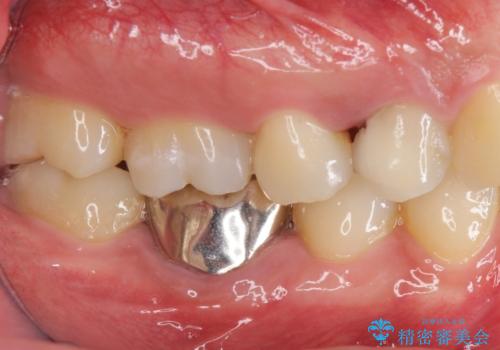

- 他の歯を治療中にレントゲン写真を撮ったところ虫歯を発見。

どうせなら1つ奥の銀歯も白くしたいとのご希望があり、2本ともセラミックにて治療をしていくことになりました。

虫歯治療に加え、奥の銀歯も同時にやり替えました。